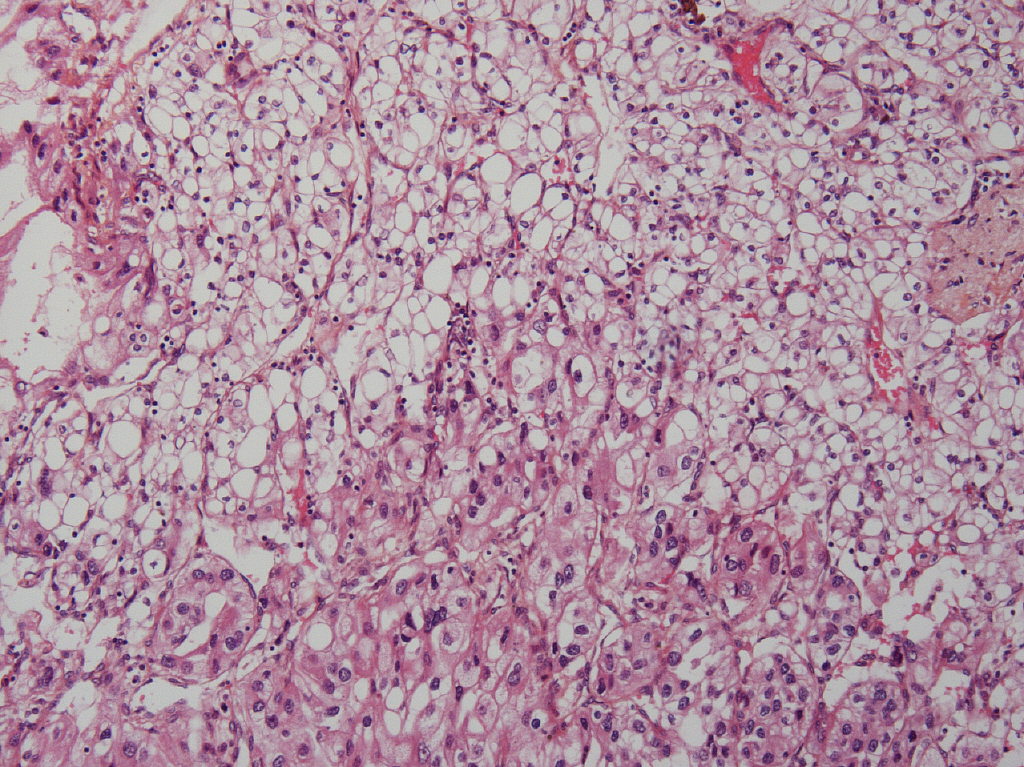

Consensus grade: WHO/ISUP grade 3

Clear cell carcinoma with different grades